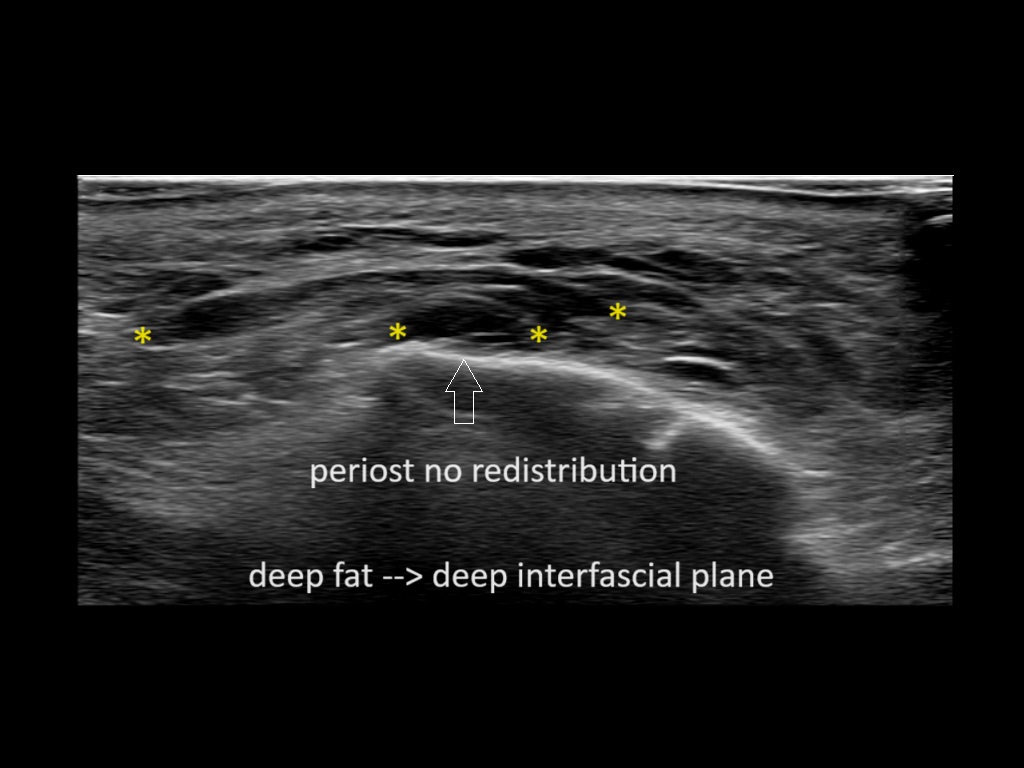

Filler behavior - Temple zygoma US

Study the first image to recognize the different layers. If you are sure about the layers, swipe to the second image to view the answer (if applicable).